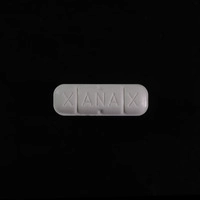

Database of Ecstasy pill reports contains lab and user data. Test results are warnings. No substance is 100% safe. Test it before you ingest it. Get a test kit.

Dislcaimer: The information provided on this page is not intended to promote drug use. Many of the substances mentioned are illegal under domestic and international law and possession of these substances is punishable by law. Never assume that a substance is safe. Ecstasy pills (extasy, XTC, molly) are expected to contain MDMA but concentration, purity and adulteration vary greatly, even if aquired from the same source or if bear seemingly the same characteristics. Chemical Safety sp. z o.o. strongly advises against the use of any psychoactive substance – legal or illegal. Consuming psychoactive substances is always an avoidable risk to your health.